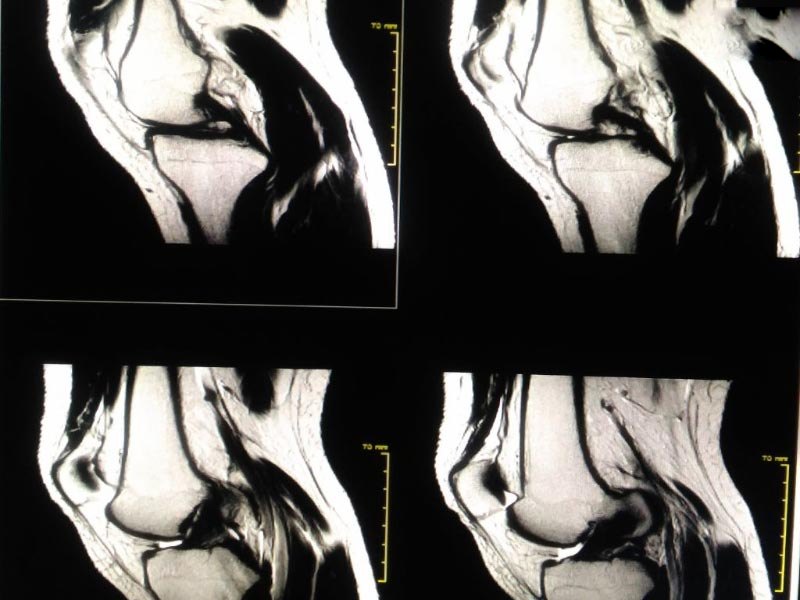

• Chẩn đoán hình ảnh: Kết hợp với kiểm tra lâm sàng, bác sĩ có thể yêu cầu thực hiện các xét nghiệm hình ảnh như siêu âm, chụp X-quang, hoặc chụp MRI để xác định nguyên nhân gây tràn dịch và đánh giá chi tiết hơn về tình trạng khớp.